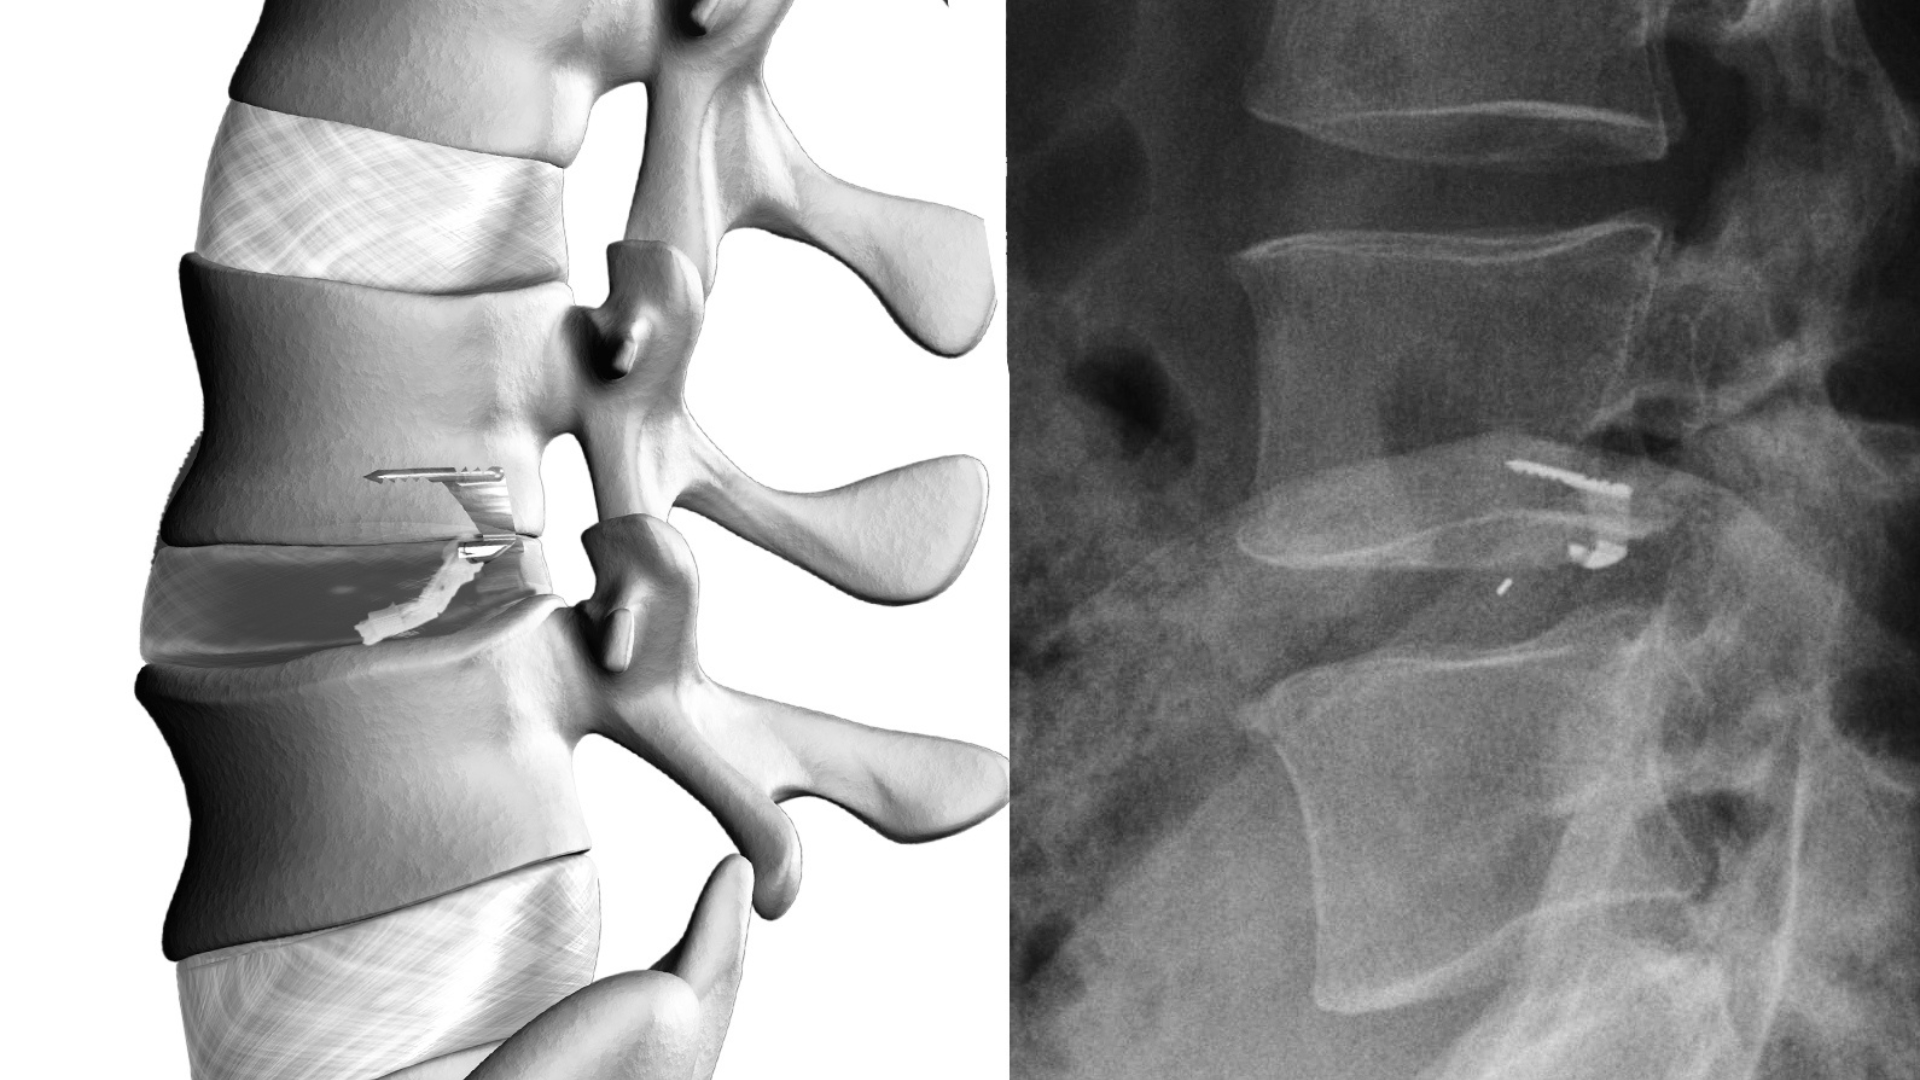

The Barricaid implant is designed to reinforce the annular defect left after discectomy. It uses a titanium anchor secured into the vertebral bone, combined with a flexible polymer shield that covers the defect in the disc wall. Together, these components create a physical barrier that helps contain remaining disc material.